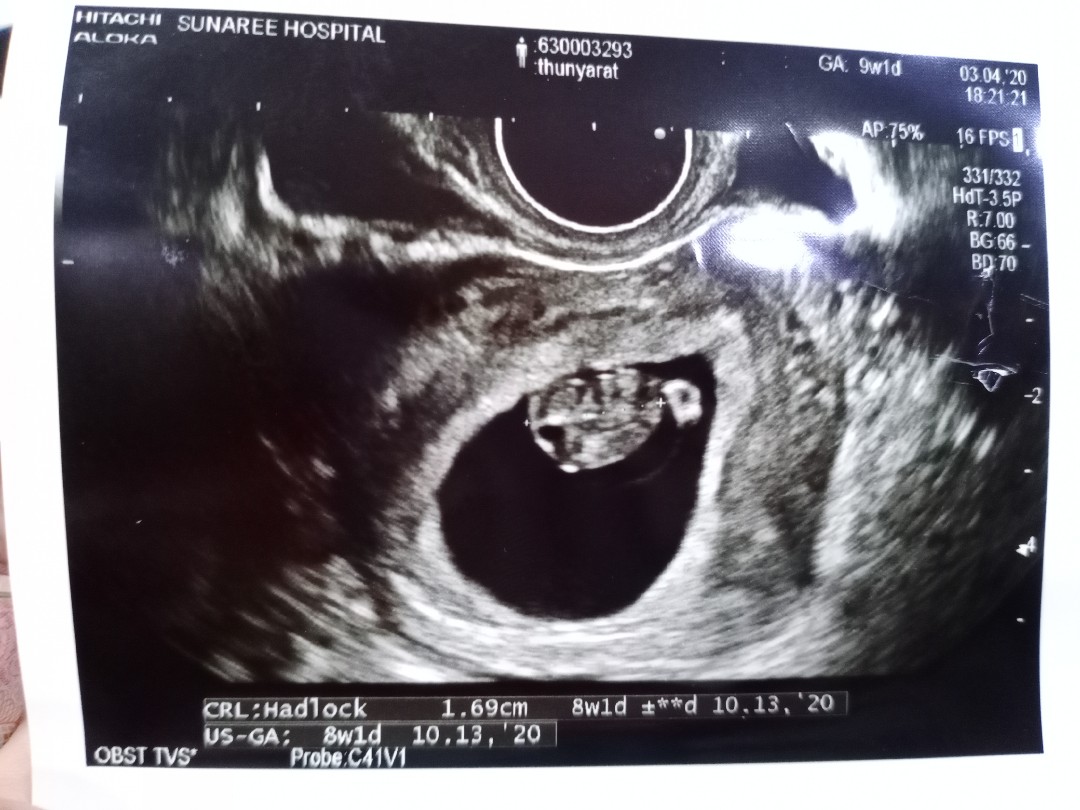

ตอน8วีคคะ